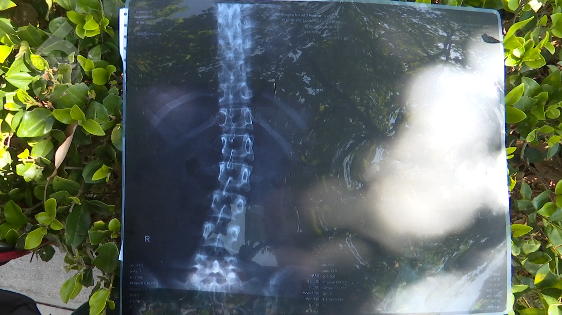

检查后,医生诊断小丽腰椎骨折、脊柱侧弯,采取保守治疗,她需绝对卧床8周,饮食、大小便都得在床上处理,3个月后才可进行正常活动。